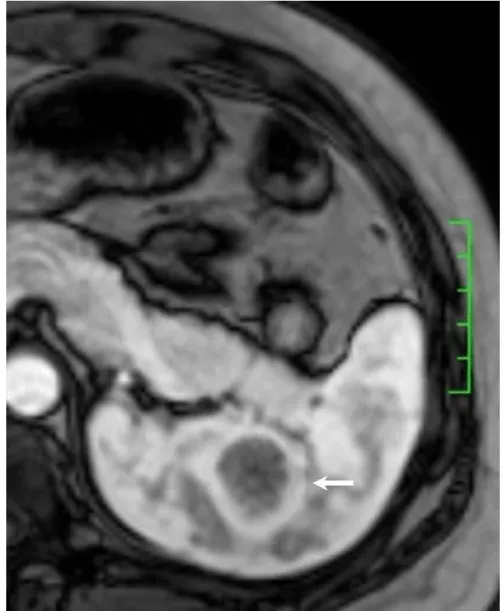

Solitary well-circumscribed masses were detected in all the five patients by ultrasound. One mass was of hypoecho, while the remaining masses were of hyperecho with posterior enhancement (Figure 1A). The maximum diameter ranged from 3.0 cm to 9.0 cm. At CT scanning, two masses appeared as hypodense (Figure 1B) and one was isodense (Figure 2A) to the normal spleenic parenchyma. In the two patients who received MR imaging, masses were isointensity at T1 weighted images (Figure 3A) and hypointensity with scattered sign void spots at T2 weighted images (Figure 3B). After intravenous injection of the contrast materials, all the five masses presented circle enhancement at arterial phase (Figure 3C and Figure 4A), while peripheral enhanced node was noted in one mass (Figure 2B). The circle enhancement persisted and radical line enhancement were observed at portal vein phase in 3 cases (Figure 1C) and progressive filling in was seen in two cases (Figure 2C). At delay phase of MR imaging, one lesion showed obvious enhancement with stellate low signal scar in the center comparing with surrounding splenic parenchyma (Figure 3D), while the other demonstrated central and circle enhancement to form a spoke-like appearance (Figure 4B). At delay enhanced CT scanning, two masses were isoattenuation to the surrounding splenic parenchyma (Figure 2D) and one lesion kept as hypoattenuation but with radial enhanced lines and enhanced circle to form a spoke-like appearance.

At pathological examination, all the masses were well demarcated on gross cut surface. A central stellate scar with peripheral interspersed dark brown nodules and the whitish intervening fibrous bands was noted to form spoke-like appearance (Figure 3E), which was well correlated with CT and MR imaging findings at enhancement. Microscopically, these angiomatoid nodules were surrounded by dense concentric collagen fibrous stroma and dispersed stromal cells with oval-to-spindle nuclei and scanty cytoplasm (Figure 3F). The abunden fibrous stroma may result in hypointensity at T2 weighted MR images. Hemosiderin was noted in the angiomatoid nodules (Figure 3G), which might contributed to signal void at T2 weighted MR images.

It usually affects middle-aged adults [6] and it is commonly found incidentally on radiographic imaging, or during operation for an unrelated condition. In present series, the patients are middle-aged adults without any related symptoms and the lesions were detected incidentally at routine ultrasound of health examinations. On ultrasound, manifestations of SANTs are vary widely from heterogeneous echo-texture with hyperechogenic, hypoechogenic, or isoechogenic appearing lesions, which are unspecific [7,8]. CT and MRI can show some characteristic features of SANTs, which include a solitary well demarcated mass with early peripheral enhancemant with radiating lines and progressive enhancement at the delay phase, and hypointens at T2 weighted MR images [2,3,5,9-13]. These features reflect the underlying pathological changes of scattered angiomatoid nodules separated and surrounded by sclerotic fibrotic stroma [10]. In present series, we also observed these characteristic features with well correlation to pathological findings. Circle and spoke-like enhancement can be contributed to fibrotic stroma surrounding and separating the angiomatoid nodules. The sclerotic fibrotic stroma may also result in isodense on CT, isointensity on T1 weighted images and hypointensity on T2 weighted images of MR imaging. The signal void spots at T2 weighted MR images have not been described at other literatures and may be contributed to hemosiderin deposition due to magnetic susceptibilty artifact.